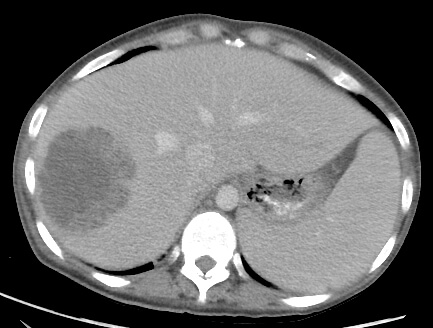

54 year old male who presents with fever, right upper quadrant pain, and an elevated WBC count.

Comment: This case of a liver abscess shows similar steps to case #1 during a percutaneous abscess drainage. In the third image, the markers we use for localization are evident. When these bands are laid on the skin and an image is obtained, we can use them to select an appropriate point of access for the procedure.